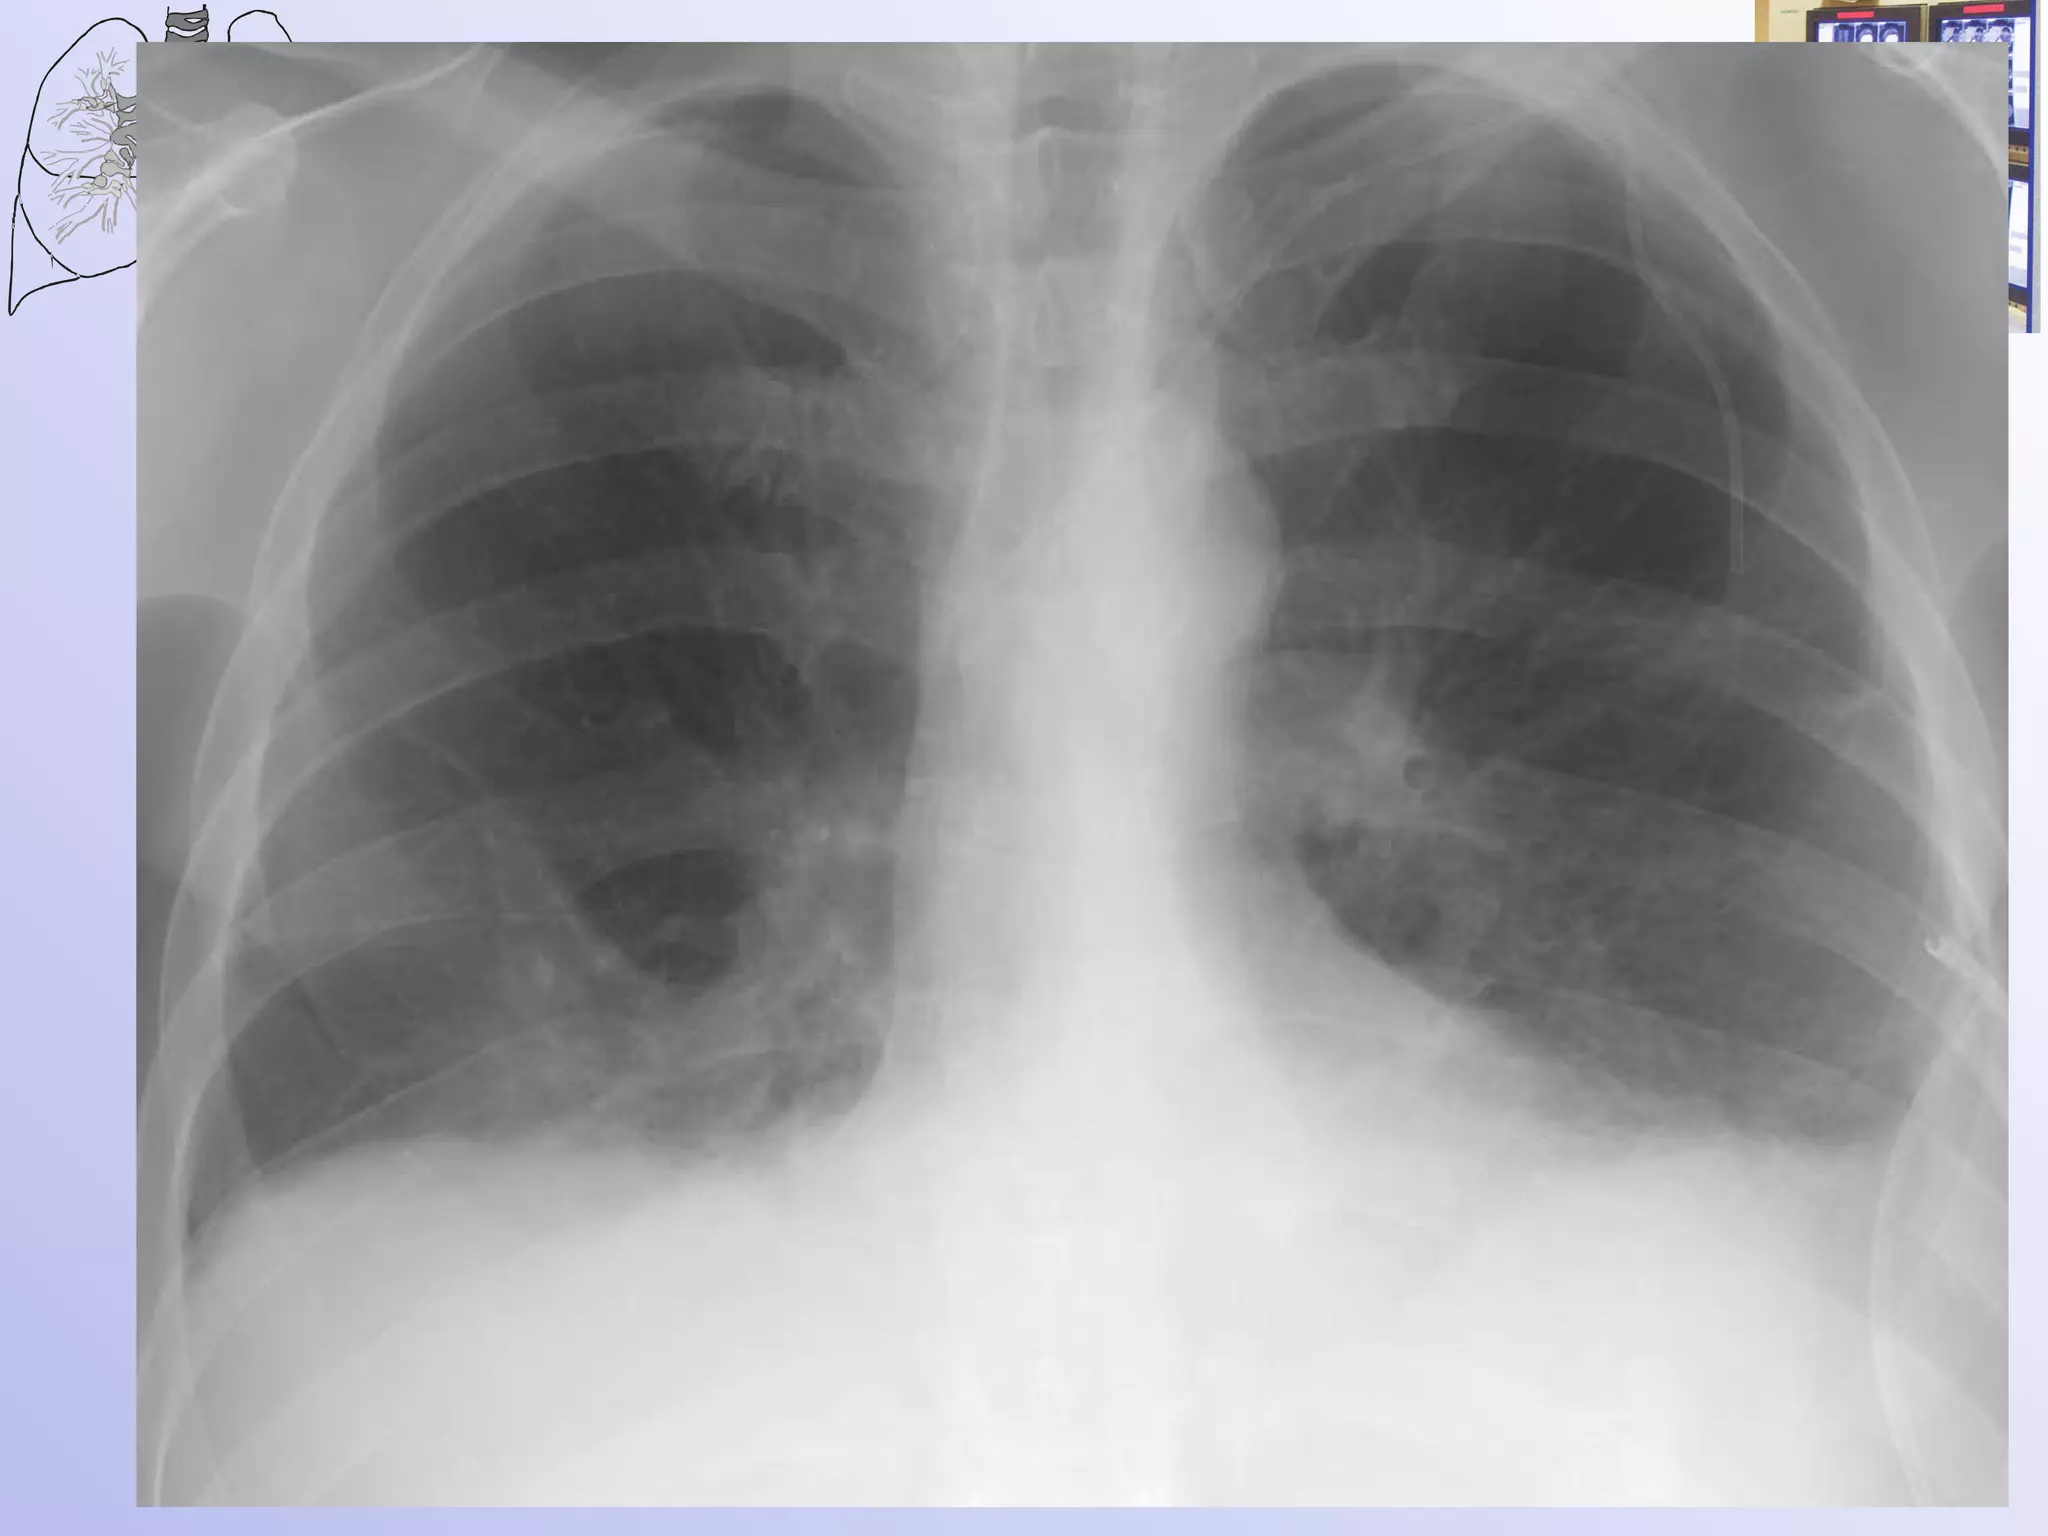

Центральный рак -эндобронхиальная  форма роста опухоли

Рентгенологическая картина при эндобронхиальном росте опухоли: Просвет бронха - конически сужен  обтурирован опухолью.  Сближение сосудов в дистальнее расположенном участке. Уменьшение объема дренируемого участка – гиповентиляция. Ателектаз.